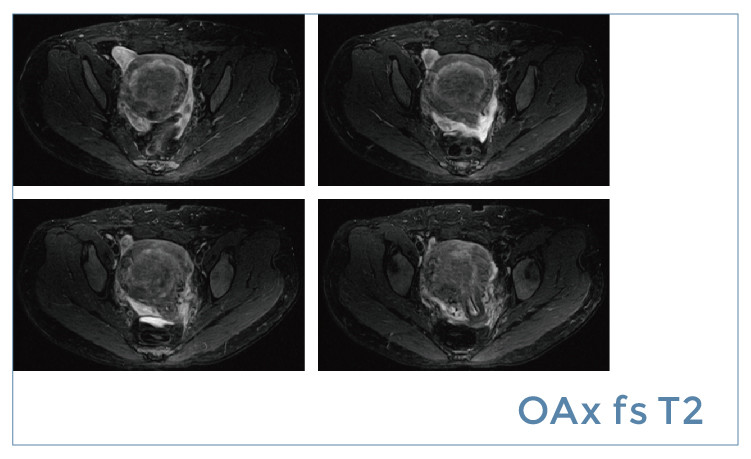

【朗润影像档案】20190621磁共振影像病例结果讨论

【朗润影像档案】磁共振影像病例分享(编号20190621)